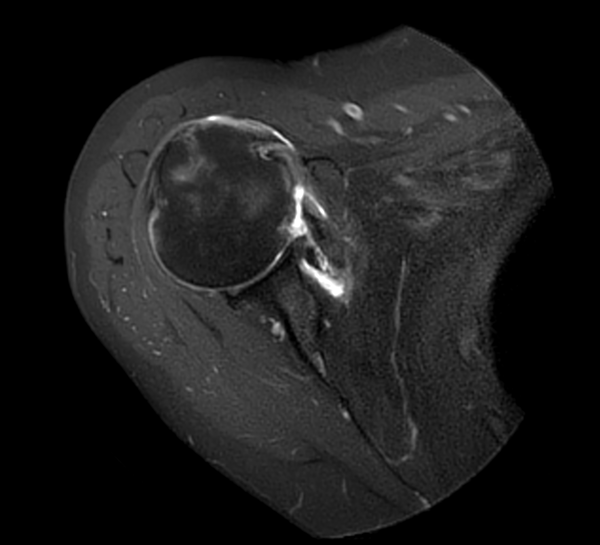

Axial MultiVane XD - PDw SPAIR